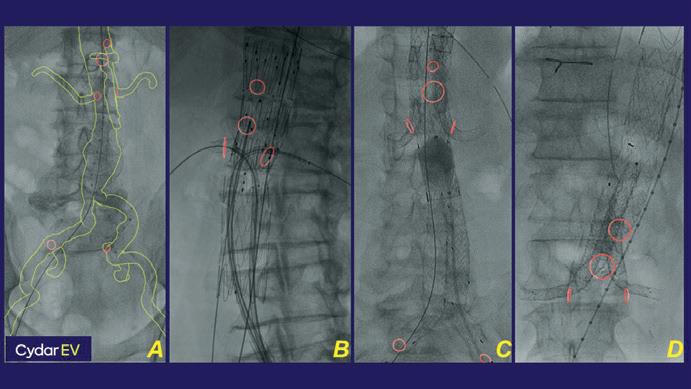

To date, we have used Cydar EV in 124

Charles J. Bailey

complex endovascular aneurysm repairs, including infrarenal, fenestrated, custom-made, and thoracoabdominal branched graft devices (Figure 3, A–D). The results of our experience are being prepared for abstract submission for the 2021 Society for Vascular Surgery Vascular Annual Meeting, including a comparative analysis of nearly 200 consecutive fenestrated endograft aneurysm repairs, with 68 using Cydar EV imaging. Our outcomes are similar to other institutional reports with Cydar EV, noting decreases in operative and fluoroscopy times, radiation dosage, total contrast volume, and number of digital subtraction angiography runs required.2 The workflow is simple. A preoperative computed tomography angiography (CTA) is uploaded to the cloud-based Cydar Vault, from which a 3D model and overlay is created (Figure 1). From imaging upload to readiness for image-guided surgery, the process can be completed in as little as 30 minutes. The ability to visualise preprocedure a 3D-overlay with skeletal reference points has improved our confidence in device orientation and procedural planning for endovascular aneurysm repair. Enabling fluoroscopy brings the Intelligent Map on-screen, with options to view markers for branch vessel origin, true lumen outline, or both (Figure 2A; images formatted for illustration). If wire or device positioning creates vessel deformation, the AI machine learning corrects for morphology, with the system also allowing operator-driven adjustments to the overlay map (Figure 2A, 2B). Adjusted Maps are marked with a colour change to the overlay, with the ability to reference or return to the preoperative map at all times. If collimation or magnification prohibits adequate view of reference vertebral bodies, a last verified map feature allows for continued overlay (Figure 2C). With Cydar EV, the spectrum of our aortic endovascular procedures (Figure 3) is being performed more efficiently, with increased confidence, and as a safer intervention for both patient and practitioner.

Anticlockwise from the top: Figures 1, 2, and 3, showing the Cydar EV imaging interface